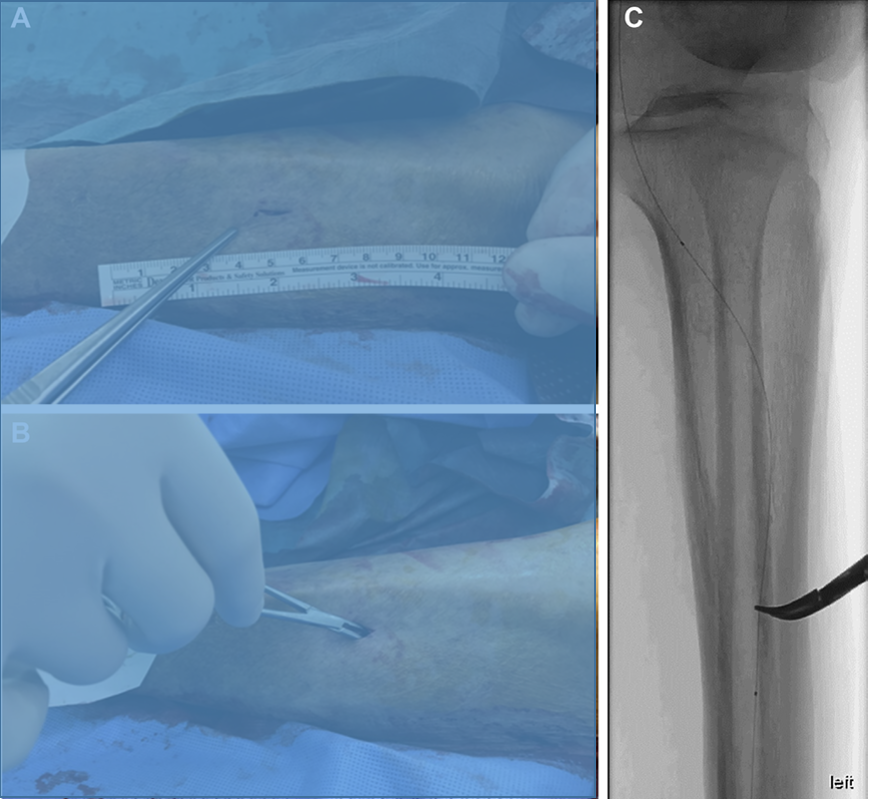

a、b. 内PIERCE技术示意图。图a显示,通过建立顺行入路部位与远端穿刺部位之间的导丝外置化,或通过顺行球囊导管在钙化病变近端锚定逆行导丝,实施远端BTK或BTA穿刺的双向入路。图b显示,从远端穿刺部位沿导丝将20G穿刺针置入动脉内,小心地边旋转边推进20G穿刺针,数次穿过钙化病变。

a–f. 器械输送困难的代表性病例。术前血管造影(a)显示胫后动脉(PTA)长段慢性完全闭塞(CTO)。图b显示,从PTA远端的逆行导丝穿过CTO病变并被外置化。低剖面球囊导管无法穿过钙化病变(虚线)。图c显示内PIERCE技术。图d显示低剖面球囊穿过并扩张钙化病变。图e显示通过长球囊导管实现充分的病变扩张。最终血管造影(f)显示PTA成功重建血运。